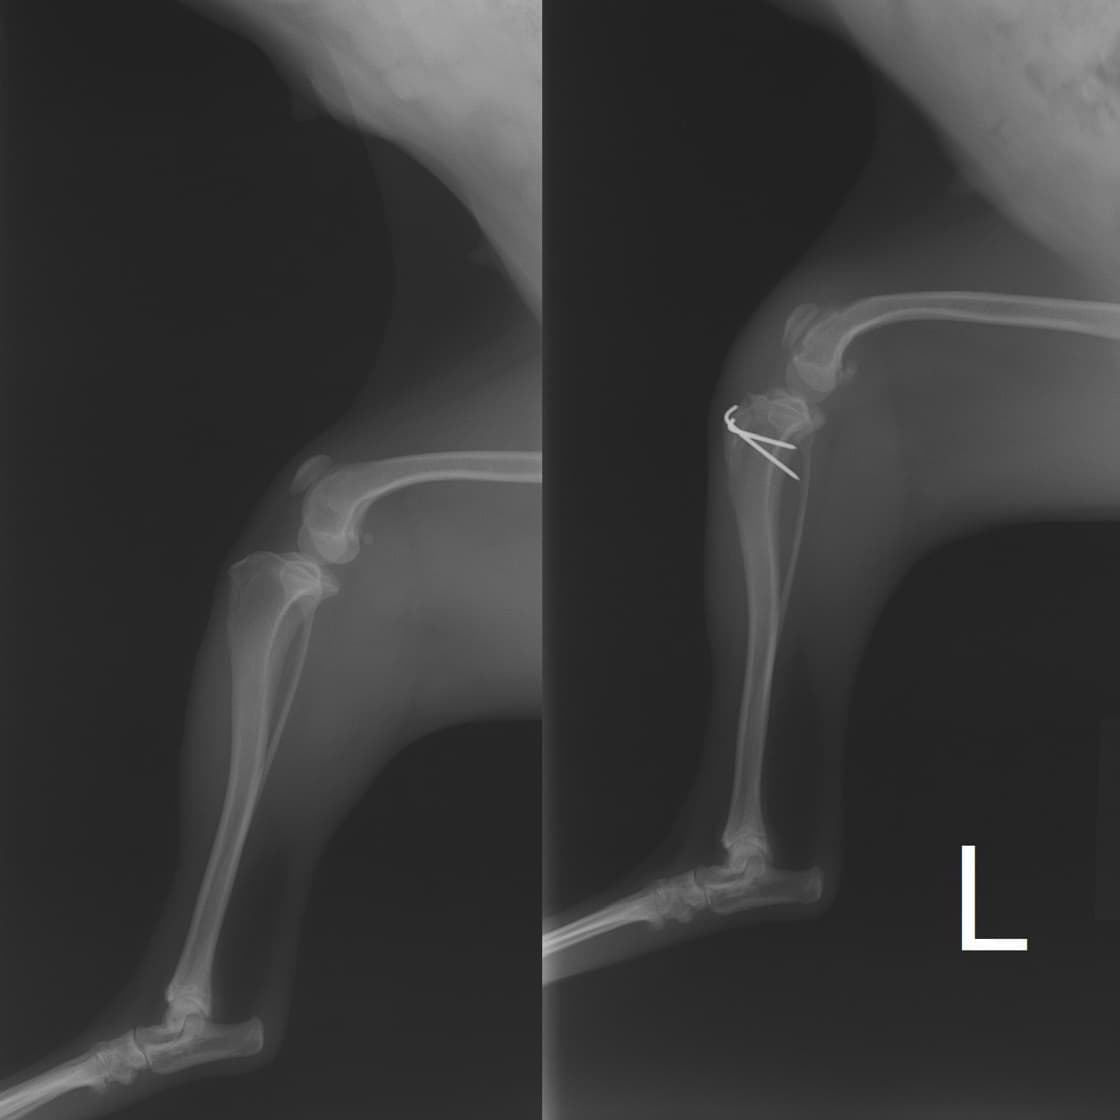

■ 症例20 ポメラニアン 8ヶ月 1.8kg

左右膝蓋骨脱臼 グレードⅢ

2ヶ月前から間欠的跛行が認められ、両膝の膝蓋骨脱臼整復術を行った。

手技は縫工筋及び内側広筋の解放、脛骨粗面の外側転位、滑車ブロック形造溝術、内外側関節包の縫縮を選択し実施した。

右側の膝蓋骨脱臼は上記手技で整復されたものの、左側はそれのみでは膝蓋骨が浮く様子が認められた。その為、PDS縫合糸にて膝蓋靱帯を1糸のみ縫合し、靱帯の縫縮を行った。

膝蓋骨脱臼は膝関節における膝蓋骨の内外側の脱臼と定義されるが、時として単純な内外の脱臼ではなく、膝蓋骨が大きく前方に浮き上がるように脱臼する場合がある。特にトイプードルやポメラニアンといった犬種に多く認められる。

内側脱臼に加えて前方への浮き上がりを矯正する為に、従来より脛骨粗面転移により膝蓋靭帯を外方と下方に引っ張り、固定する方法を選択する。膝蓋骨の前方への浮き上がりが軽度の場合は、従来法ではなく関節包の縫縮で対応していた。しかし、一部の症例で膝蓋骨の動きが悪くなり伸展機構が円滑に機能せずロボット様歩行になるケースがあった。

その為、膝蓋靭帯自体を縫縮する方法を採用した。この方法により、膝関節の伸展機構を妨げず膝蓋骨の軽度の浮きを矯正することが可能となった。

本症例の経過は良好である